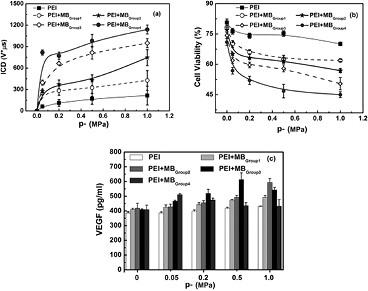

Standard image High-resolution image3.6. US-facilitated VEGF165 transfection assessments for SPIO-albumin microbubbles

Beyond a dual-modality imaging probe, the proposed SPIO-albumin MBs were also designed as a therapeutic agent. Thus, the enhancement effect of SPIO-albumin MBs on US-facilitated VEGF165 transfection effect was also evaluated in vitro under varied SPIO concentrations. In the experiments, the tested samples were divided into five series: (1) HEK 293 T cells mixed with bPEI:VEGF165 complexes only; and (2)–(5) cells + bPEI:VEGF165 + MBs in Group 1–4 (i.e. SPIO-concentration = 0, 19.6, 114.7 and 292.0 μg ml−1, respectively). 1 MHz US exposures were applied to the tested samples with varying acoustic driving pressures (p-).

In order to examine the capability of SPIO-albumin MBs on US-facilitated gene transfection, VEGF165 protein secreted into the supernatant of treated cell suspensions was quantitatively measured using ELISA assay and the cell viability was evaluated by CCK-8 assessments. Meanwhile, MB IC energy accumulated during US exposure period was quantified as ICD based on PCD measurements, since MB IC activities have been claimed to play an important role in US-facilitated gene/drug delivery through sonoporation (Miller et al 2002, Van Wamel et al 2006, Zhang et al 2013). The measured ICD, cell viability and VEGF165 transfection efficiency are plotted in figure 7, as a function of p-. It is clearly shown in figure 7(a) that ICD generally increases with the increasing p- and the addition of MBs with higher SPIO concentrations. Cell viability can be expressed as a percentage of the number of viable cells in the experimental samples divided by the number of viable cells in the control samples. As shown in figure 7(b), if sham treatments (i.e. p- = 0) are applied, about a 20% reduction of cell viability might be attributed to the cytotoxicity of bPEI without adding MBs (Fischer et al 1999). However, a slight decline of cell viability (less than 10%) can be observed by adding MBs with increasing SPIO concentration (i.e. from 19.6 to 292.0 μg ml−1). After US exposures, cell viability can be significantly lowered with the increasing p- and SPIO concentration (a maximum reduction of 56.5% is observed under current experiment conditions). Figure 7(c) shows VEGF165 transfection efficiency measured for individual samples. For the sham treatments (p- = 0), VEGF165 transfection is mainly facilitated by bPEI, thus there is no obvious enhancement observed with the addition of MBs. For cells mixed with bPEI:VEGF165 complexes only, US exposures might slightly benefit bPEI:VEGF165 transfection without MB IC activities. As albumin-shelled MBs are added into the suspension (viz, cells mixed with bPEI:VEGF165 complexes with MBs in Group 1), the DNA transfection efficiency can be statistically raised, compared with the samples mixed with bPEI:VEGF165 only. When cells were mixed with bPEI:VEGF165 complexes and MBs in Group 2, the coating of SPIOs on MB shells (effective SPIO concentration = 19.6 μg ml−1) significantly improves US-facilitated VEGF165 transfection. However, as the concentration of SPIOs in MB shells increases to 114.7 μg ml−1 (viz, cells mixed with bPEI:VEGF165 complexes with MBs in Group 3), the transfection efficiency initially increases with the increasing p-, then reaches a peak level of 613.1 ± 46.02 pg ml−1 at p- = 0.5 MPa. As p- is continuously raised to 1.0 MPa, the measured VEGF165 concentration, in turn, drops to 542.9 ± 17.26 pg ml−1. When SPIO concentration further increases to 292.0 μg ml−1 (viz, cells mixed with bPEI:VEGF165 complexes with MBs in Group 4), the measured VEGF165 concentration will increase first, then decrease with the increasing p-, although the peak value appears even earlier at p- = 0.05 MPa. Thus, it is obvious that, compared with cell viability and ICD, much more complicated variation happens in VEGF transfection efficiency assessments.

Figure 7. The dependences of ICD (a), cell viability (b) and VEGF165 transfection efficiency (c) on acoustic driving pressure measured for SPIO-albumin MBs with varied SPIO concentrations. 1 MHz US exposures were performed at fixed 20-cycle pulse length and 250 Hz PRF. The total treatment time for each sample was 20s. The figure plots the results for five replicated measurements.

Download figure:

The MRI (figure 5) and US imaging (figure 6) studies have confirmed that, with facile surface modification, the presence of Fe3O4 in MB shell provides enough acoustic and magnetic susceptibility to albumin-shelled UCA MBs to accomplish superb US and MR detectability and sensitivity. To target at multifunctional imaging and drug delivery agents, the therapeutic capability of SPIO-albumin MBs on VEGF165 transfection was also examined in the present work. PEI:VEGF165 complexes were used in this work instead of naked DNA because PEI has been shown to be a relatively efficient non-viral vector and because the synergistic effect of US and PEI on DNA transfection has also been reported in previous work (Deshpande and Prausnitz 2007, Qiu et al 2010, Zhang et al 2013). As reported, US-induced IC activities, which could be dramatically enhanced by the addition of UCA MBs, can transiently enhance cell membrane permeability through sonoporation processes to facilitate the entry of foreign gene/drugs into cells. In order to achieve a better understanding of the mechanisms involved in SPIO-albumin- MB-medicated VEGF165 transfection induced by US exposures, the 'amount' of IC energy cumulated over the US exposure duration (i.e. ICD), cell viability after treatments and effective VEGF165 transfection efficiency were all systemically assessed here at varied p- and SPIO concentration in MB solutions.

For cell samples treated under US sham status, only a slight decrease in cell viability could be observed with the increasing SPIO concentration, which suggests that the current SPIO-albumin MBs are safe for biological application with relatively low cytotoxicity. With US exposures, an increase in p- and SPIO concentration coated in MBs would lead to a significant increase in ICD (figure 7(a)) and decrease in cell viability (figure 7(b)). The enhancement of ICD at higher p- could be simply explained by the greater acoustic energy delivered to the tested samples, which is consistent with previous reports (Qiu et al 2010, Zhang et al 2013). The rising trend of the ICD dependence on SPIO concentration might result from the enlargement of MB size and the reduction of MB stiffness as more SPIOs embedded in the bubble shells. The above MB size (figure 3) and AFM elasticity (figure 4) assessments have shown that, with the lower SPIO concentration, smaller but stiffer MBs might be formed when other conditions remain unchanged. It is feasible that MBs with greater stiffness would have more rigid shells, which could result in an increased resistance to MB collapse and consequently hinder its IC activities. Thus, it is reasonable to expect stronger IC activities for MBs loaded with greater SPIO concentration. Actually, Tung et al (2011) also noticed, in their in vivo blood-brain barrier opening studies, that greater ICD could be obtained with larger bubbles, which is consistent with current observations.

An interesting point worthy of notice is that, unlike nearly monotonic transitions of ICD and cell viability with the increasing p- and SPIO concentration, the variation trend of VEGF165 transfection efficiency seems much more complicated (figure 7(c)). To explore this phenomenon in depth, the correlations between transfection efficiency, cell viability and accumulated IC energy, were studied by analyzing the pooled experimental data. As shown in figure 8(a), significant linear correlation can be observed between the decrease of cell viability and the ICD enhancement. More importantly, it is clearly illustrated in figure 8(b) that, rather than the complex discrepant variations shown in figure 7(c), the DNA transfection efficiency initially increases linearly with the increasing ICD in a certain range. Then, after reaching its peak value at an ICD of about 820 V μs, DNA transfection efficiency tends to drop if the ICD increases continuously. As suggested by previous work, US-facilitated DNA transfection is mainly induced by sonoporation and high correlation could be observed between sonoporation pore size and the measured ICD (Qiu et al 2010). The transient pores generated on the cell membrane should be beneficial for cells to uptake the genetic material, which can lead to the enhancement of DNA transfection efficiency. However, if the IC energy exceeds a certain level (e.g. ICD > 820 V μs), overlarge pores might be generated, which in turn results in unrecoverable damage to cells. As a consequence, the cell viability would be impaired, thereby significantly lowering the DNA transfection efficiency.